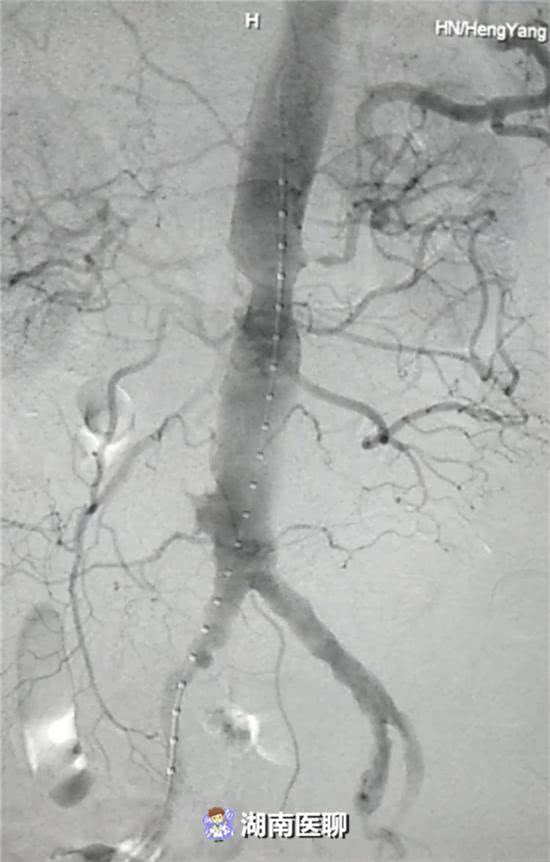

近日,在李珍發(fā)博士的帶領下,衡陽市中心醫(yī)院血管介入科專家涂宏手術小組成功行腹主動脈覆膜支架隔絕術血管介入治療。

血管介入科排除各種困難,在麻醉科協(xié)作下行腹主動脈瘤覆膜支架隔絕術(“褲衩”支架植入)。

(血管介入科行腹主動脈瘤覆膜支架隔絕術)